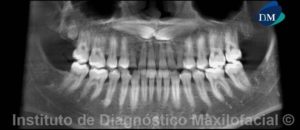

Paciente de sexo masculino de 54 años de edad, el cual manifiesta no presentar síntomas y es referido para la respectiva evaluación radiográfica previo al tratamiento con implantes.